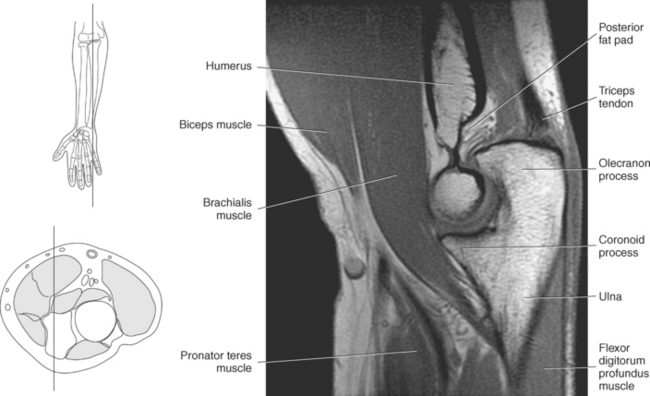

The ulna is located medial within the forearm. The proximal ulna consists of the olecranon and coronoid processes and the trochlear and radial notches. The superficial dorsal surface is formed by the hook-shaped olecranon process, which is the attachment site for the triceps brachii. The trochlear notch is a half-moon-shaped concave articular surface that curves around the trochlea of the humerus. This articulation allows for flexion and extension of the elbow. Located on the anterior portion of the distal end of the trochlear notch is a small beaklike process called the coronoid process. Just distal and lateral to the coronoid process is a flattened depression called the radial notch. It is covered by articular cartilage for articulation with the radial head. Immediately distal to the coronoid process is a roughened bony surface termed the ulnar tuberosity. The tendon of the brachialis muscle inserts on both the coronoid process and the ulnar tuberosity (Figures 9.72, 9.73, 9.75, and 9.76).

The entire elbow joint is surrounded by a relatively loose joint capsule that allows for the movements of flexion and extension. The joint capsule is weaker anteriorly and posteriorly but is reinforced medially and laterally by the strong radial and ulnar collateral ligaments (discussed in the next section). Located within the olecranon and coronoid fossas are fat pads that fill the space between the synovial membrane and joint capsule (Figures 9.77 and 9.78). The fat pads help cushion the area where the olecranon and coronoid processes move during flexion and extension of the elbow. There are two clinically important bursae located in the elbow: the olecranon bursa and the distal bicipitoradial bursa. The olecranon bursa is located within the subcutaneous tissue overlying the olecranon process (Figure 9.77). The distal bicipitoradial bursa lies between the insertion of the biceps tendon and the humerus.